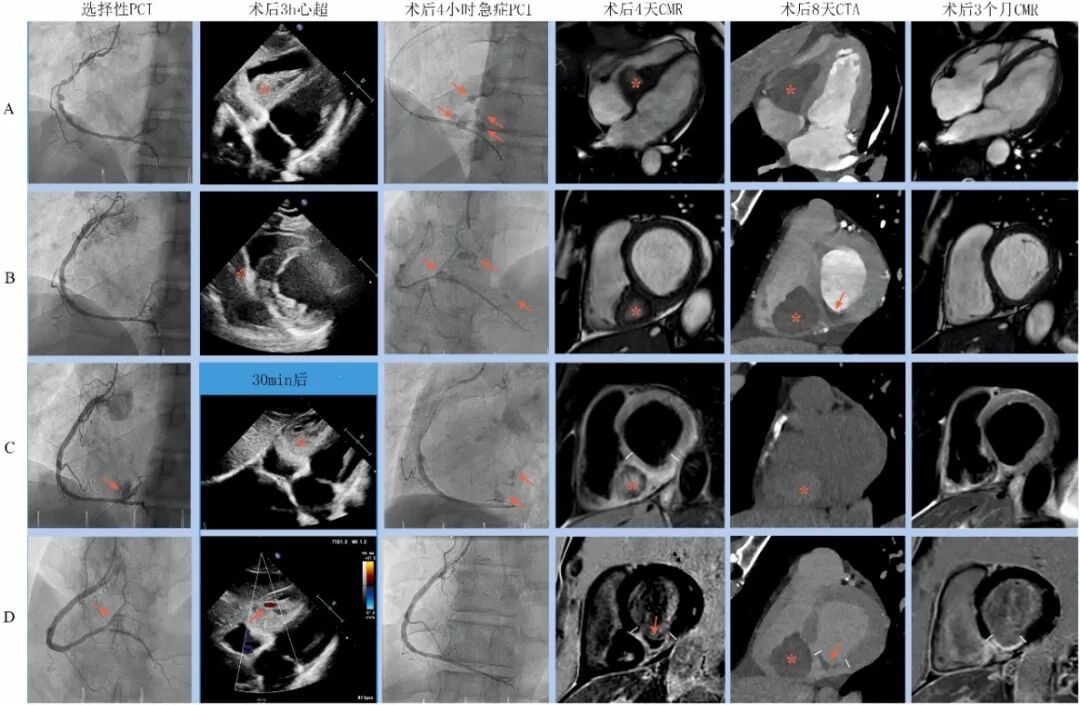

图3心肌壁内血肿的多模态成像[2]。

第一列为PCI图像,A.右冠造影;B.置入支架后;C-D 造影剂外渗。第二列为术后3小时心超,A.剑突下切面,可见室间隔血肿压迫右室;B.胸骨旁短轴切面;C-D 30分钟后复查剑突下切面心超,血肿快速进展,多普勒信号提示血流进入血肿。第三列为术后4小时再次PCI图像,A-B.紧急右冠造影可见多点外渗(箭头);C.长时间球囊封堵后依旧外渗;D 带膜支架植入,外渗停止。 第四列为第4天CMR图像,A和B分别为长轴四腔心和短轴电影,※为心肌内血肿;B.置入支架后;C.短轴T2加权,短线之间为高信号水肿,※为血肿;D短轴延迟增强,短线之间透壁性增强提示心肌梗死,箭头为微血管阻塞(MVO)。第五列为低8天CTA图像,A.注射造影剂后长轴四腔心,※为血肿,未见活动性造影剂外渗;B.相应短轴,※为血肿,箭头为微血管阻塞(MVO);C.无造影剂平扫,血肿显示为信号增强区;D短轴延迟增强,※为血肿,短线之间透壁性心肌梗死,箭头为微血管阻塞(MVO)。第六列为第3个月CMR图像,与第四列比较,可见心肌血肿完全消失(A和B),无水肿(C),慢性透壁性心肌梗死(D)